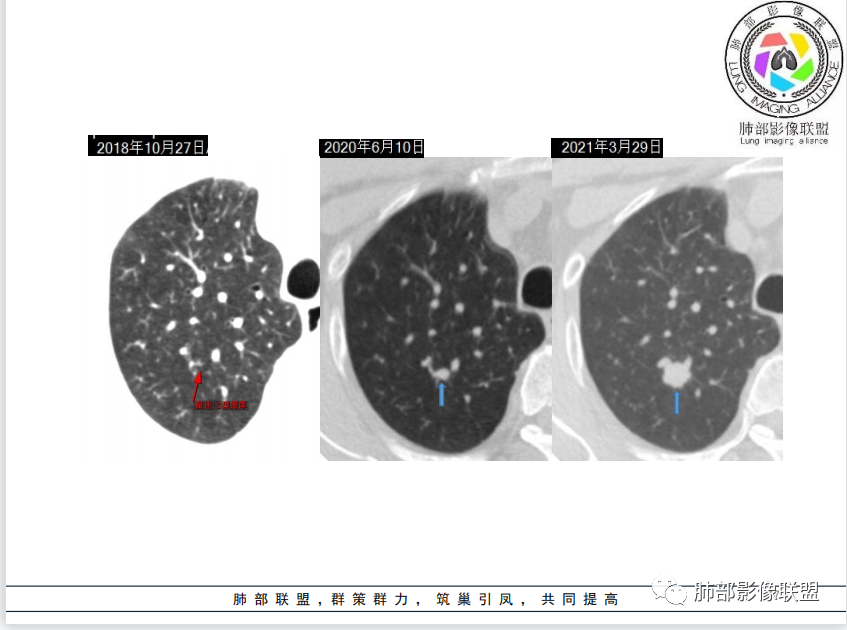

病例资料

病理结果

影像与临床

3、右肺上叶不规则实性密度为主结节影,可见浅分叶,边界隐约可辨,界面欠清晰。病灶密度欠均匀,边缘似可见磨玻璃影,未见钙化及卫星灶。

4、矢状位示病灶沿肺动脉长轴走形,边缘较平直;

6、综合分析,右肺上叶单发实性小结节,浅分叶,边界隐约可辨,未能明确与支气管关系。病灶边界不够清晰游离(与邻近肺组织多有瓜葛),加之缺乏周边征象,硬化性肺细胞瘤等良性肿瘤可能性较小。

需要鉴别的是炎性病灶(如炎性肉芽肿)与恶性肿瘤。病灶较小,恶性征象不多(小支气管阻塞、深分叶及毛刺、清楚的磨玻璃晕,张力高等等),仓促定性,未免仓促,可以定期复查是否有变化,穿刺活检也可视为积极措施,唯病灶较小,幽深不测,难度较大。

7.注意:1)血管旁实性密度小结节有时易被“瞒天过海”2)不宜轻视任何一个肺部结节。